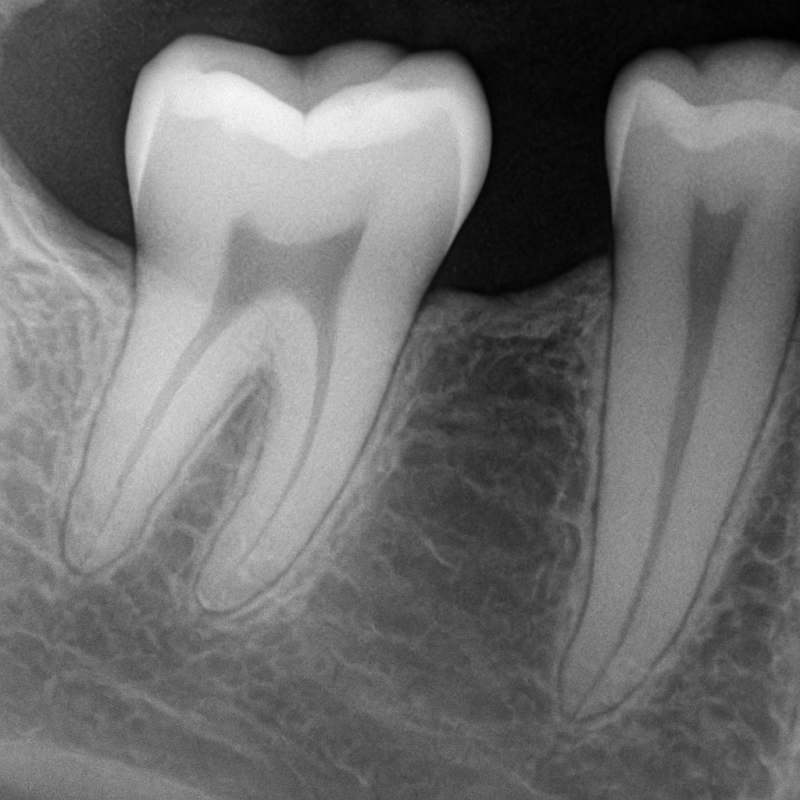

1. Meten van de pockets (de ruimte tussen tand en tandvlees)

2. Röntgenfoto’s om eventueel botverlies te beoordelen